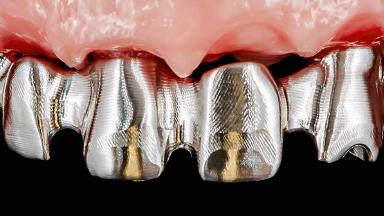

Rehabilitating an Edentulous Maxilla with a Fixed Dental Prosthesis Following Provisional Immediate Loading

This case features the flapless computer-guided placement of 7 bone-level implants, distributed to provide maximal support for the prosthetic framework. A rigid one-piece metallic framework was utilized as an interim restoration to reduce the risk of fracture associated with this prosthetic design. As part of the clinical examination, the SAC Assessment Tool was used, resulting in a surgical and restorative risk classification as “complex”.

Abutment Type Standard

Prosthesis Type FDP